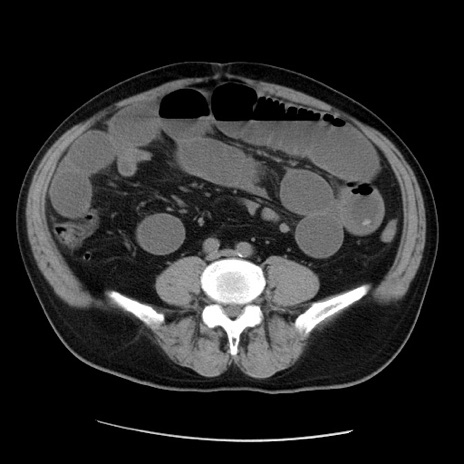

症例20(横断像)

【症例】 60歳代男性

【主訴】 腹部膨満、嘔吐

【現病歴】5日前頃より倦怠感を認め食事量減少し4日前の朝嘔吐、食事摂取困難となった。 3日前近医受診し点滴施行され整腸剤などを処方された。 当日他院を受診し、腹部膨満著明、炎症反応の上昇(CRP10.8、WBC11200)あり、紹介受診となる。

【身体所見】 意識JCS1 受け答えがはっきりしないBP 111/57mHg、 P 67bpm、、BT35.2°C、SpO2 97%(RA)、 腹部:膨隆、打診で鼓音あり、全体的に圧痛有り、腸蠕動音(-)、反跳痛ははっきりせず。

【データ】WBC 11400、CRP 14.20